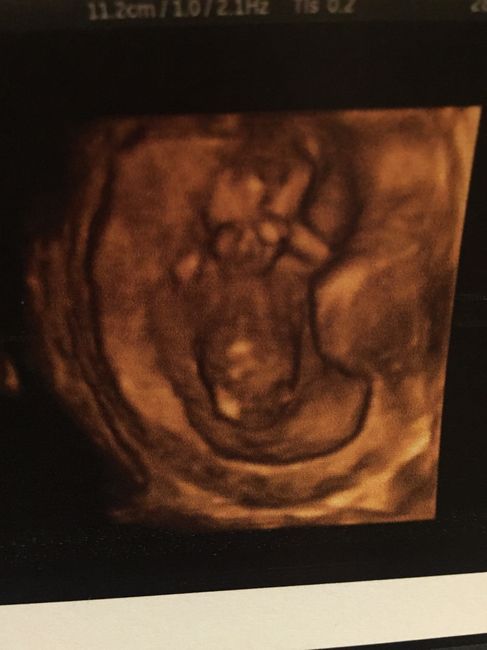

13+1 e translucenza

Da Valeria , Il 16 Gennaio 2016 alle 15:13

Il nostro/a piccolo/a sta bene siamo felicissimi anche se durante la tn é stato davvero poco collaborativo si é perfino grattato le chiappe in diretta.. :...